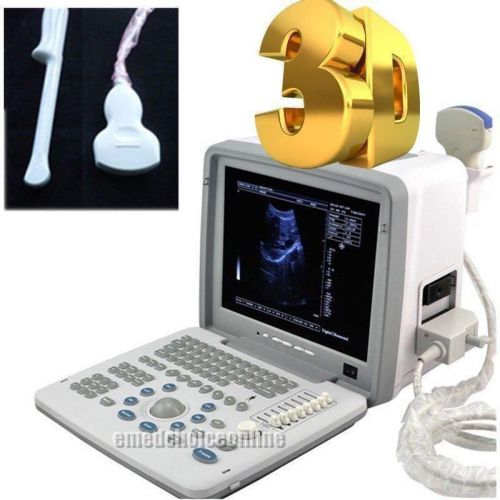

3D Portable Notebook Digital Laptop Ultrasound machine Scanner CONVEX PROBE

New 12.1 Full Digital Portable Ultrasound Scanner trans vaginal 3D workstation

3D Full Digital Portable Ultrasound Scanner convex & Transvaginal 3D workstation

NEW Diagnostic Ultrasound Scanner MACHINE +3D function + convex sensor pregnancy

2015 Digital Laptop Ultrasound Scanner+Convex+ Transvaginal Probe+ 3D image-DHL